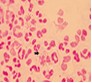

淋病的有哪些危害?淋病是常見的性病之一,和其他性病一樣,其主要傳播途徑也是性直接接觸。有些淋病患者則認為,可能是自身免疫系統(tǒng)將淋病病清除了,可以不用治療。然而實際上,淋球菌卻依然存在體內(nèi),而且正朝著慢性病變的方向發(fā)展,并伺機傳染他人,造成更大范圍的傷害。 陜西生殖醫(yī)學醫(yī)院在此特別提醒淋病患者,不要以一時的病情好轉(zhuǎn)就判定沒有問題了,而要堅持治療,只有在完完全全確定已清除病毒后才可以放心。

淋病的有哪些危害:

1、容易使淋球菌產(chǎn)生耐藥性,或病菌隱藏于泌尿生殖系統(tǒng)的腺體,引起前列腺炎、精囊炎、附睪炎、宮頸炎或附件炎等,并造成尿道黏膜損傷,出現(xiàn)上述不適癥狀。

2、合并其他感染:臨床上常見的有衣原體、支原體及表皮葡萄球菌感染。

3、淋病沒治好就繼續(xù)過性生活,使病菌傳染給對方,伴侶在不知情的情況下疏于治療,造成與性伴侶之間反復交叉感染,癥狀遷延不愈。

4、加重心理負擔,長時間的不良心理情緒影響正常的工作和生活,大大降低生活總之,淋病的危害巨大,一定要引起重視,千萬不可馬虎大意。同時如果患上淋病不要私自用藥,一定要到良好醫(yī)院接受科學的治療,并在良好的指導下做好護理工作,為了自己也為了家人一定要謹慎又謹慎。